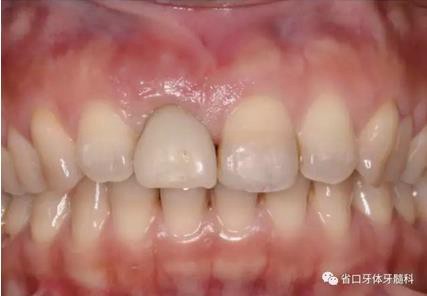

圖1 術(shù)前口內(nèi)照

圖2 術(shù)前口內(nèi)照

圖3 術(shù)前口內(nèi)照

1.?病例簡(jiǎn)介 43歲女性患者,主拆:右上前牙松動(dòng)不適數(shù)日要求修復(fù)。現(xiàn)病史:患者數(shù)年前右上前牙因“齲壞”于外院行根管治療(具體不詳),數(shù)日前牙冠松動(dòng)不適,現(xiàn)覺(jué)影響咀嚼及美觀,遂來(lái)我院要求進(jìn)一步診治。否認(rèn)高血壓、心臟病等重大疾病,否認(rèn)結(jié)核、肝炎等傳染病史,否認(rèn)手 術(shù)、輸血史等,未發(fā)現(xiàn)藥物過(guò)敏。無(wú)吸煙習(xí)慣。臨床檢查:口外觀顏面基 本對(duì)稱,皮膚無(wú)紅腫破潰,顳下頜關(guān)節(jié)區(qū)無(wú)彈響、雜音、壓痛,開(kāi)口度約 37mm,開(kāi)口型“↓”,頜下、刻下和頸部未及腫大淋巴結(jié)。中位笑線??趦?nèi)檢查,口腔衛(wèi)生可,色素(+),BOP(-),PD=2mm,上頜右側(cè)中切 牙冠部變色,冠根折斷至齦下3mm,叩不適,松動(dòng)Ⅱ°~Ⅲ°。牙齦稍紅, 齦緣水平及齦乳頭高度可,屬于中厚齦生物型,附著齦寬度約5mm,唇系帶附著可。上頜右側(cè)中切牙缺牙間隙與對(duì)側(cè)同名牙一致,約>7mm,修復(fù)空 間良好。與對(duì)頜牙覆合覆蓋正常。MCT檢查示上頜右側(cè)中切牙冠根折斷至骨 下,根管內(nèi)見(jiàn)充填物,根充不全,根尖見(jiàn)陰影,大小約3mm×3mm。牙槽窩根方可用骨量可,唇側(cè)骨壁完整,冠方骨壁厚度約1mm。